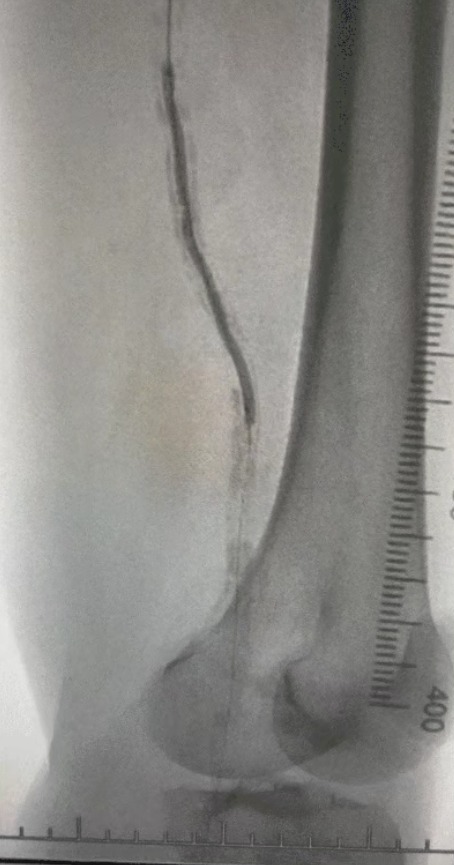

· Pencitraan preoperatif: menyebarkan stenosis parah, menyebarkan kalfikasi dalam jalan setapak anggota bawah bilateral

Mengingat kondisi vaskular yang kompleks, kami memilih sistem saluran masuk kateter balon ThorCrack periferal. Karena toleransi terbatas pasien, mengadakan prosedur intervensi pada anggota tubuh bawah dilakukan.

Prosedur pasca, stenosis arteri meningkat secara signifikan, aliran darah meningkat, dan suhu kulit mawar. Tidak ada terjadi komplikasi setelah operasi. Baik pasien maupun tim bedah sangat puas dengan hasilnya.